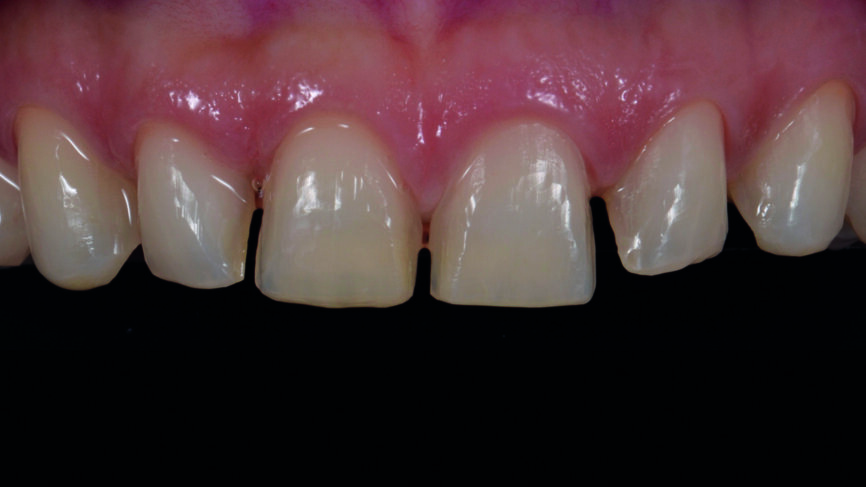

Fig. 2a : Dents antérieures après le traitement orthodontique.

Fig. 2b : Dents antérieures après le traitement orthodontique

Le traitement orthodontique proposé visait à un alignement plus favorable des dents de façon à ne requérir qu‘une préparation minimale pour la pose des facettes et à réduire le recouvrement incisif. Une année après le traitement, la patiente est revenue pour la restauration prothétique définitive (Figs. 2a et b).

Après une période de stabilisation des tissus d‘une durée de sixmois (Fig.7), un mock-up a été fabriqué au fauteuil avec le composite Telio CS C&B (Ivoclar Vivadent) (Figs. 8a et b), et les dents ont été préparées avec des clés en silicone (Figs. 9a–c). Des empreintes classiques en polysiloxane de vinyle (Fig. 10) ainsi que des empreintes numériques (scanner TRIOS de 3Shape) ont été prises (Fig. 11).